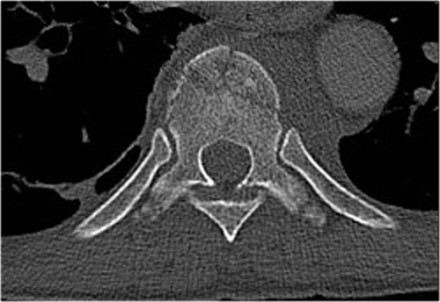

Widening of the interpedicular distance

Widening of the interpedicular distance, often a result of the sagittal fracture, is seen in 80% of burst fractures.

The lateral view shows the typical features of a burst fracture.

On the AP-view notice the subtle widening of the interpedicular distance compared to the levels above and below.

The axial CT and MRI in the same patient show the displaced fragment pressing on the thecal sac.

On the sagittal CT and MRI there are no signs of posterior ligamentous injury.